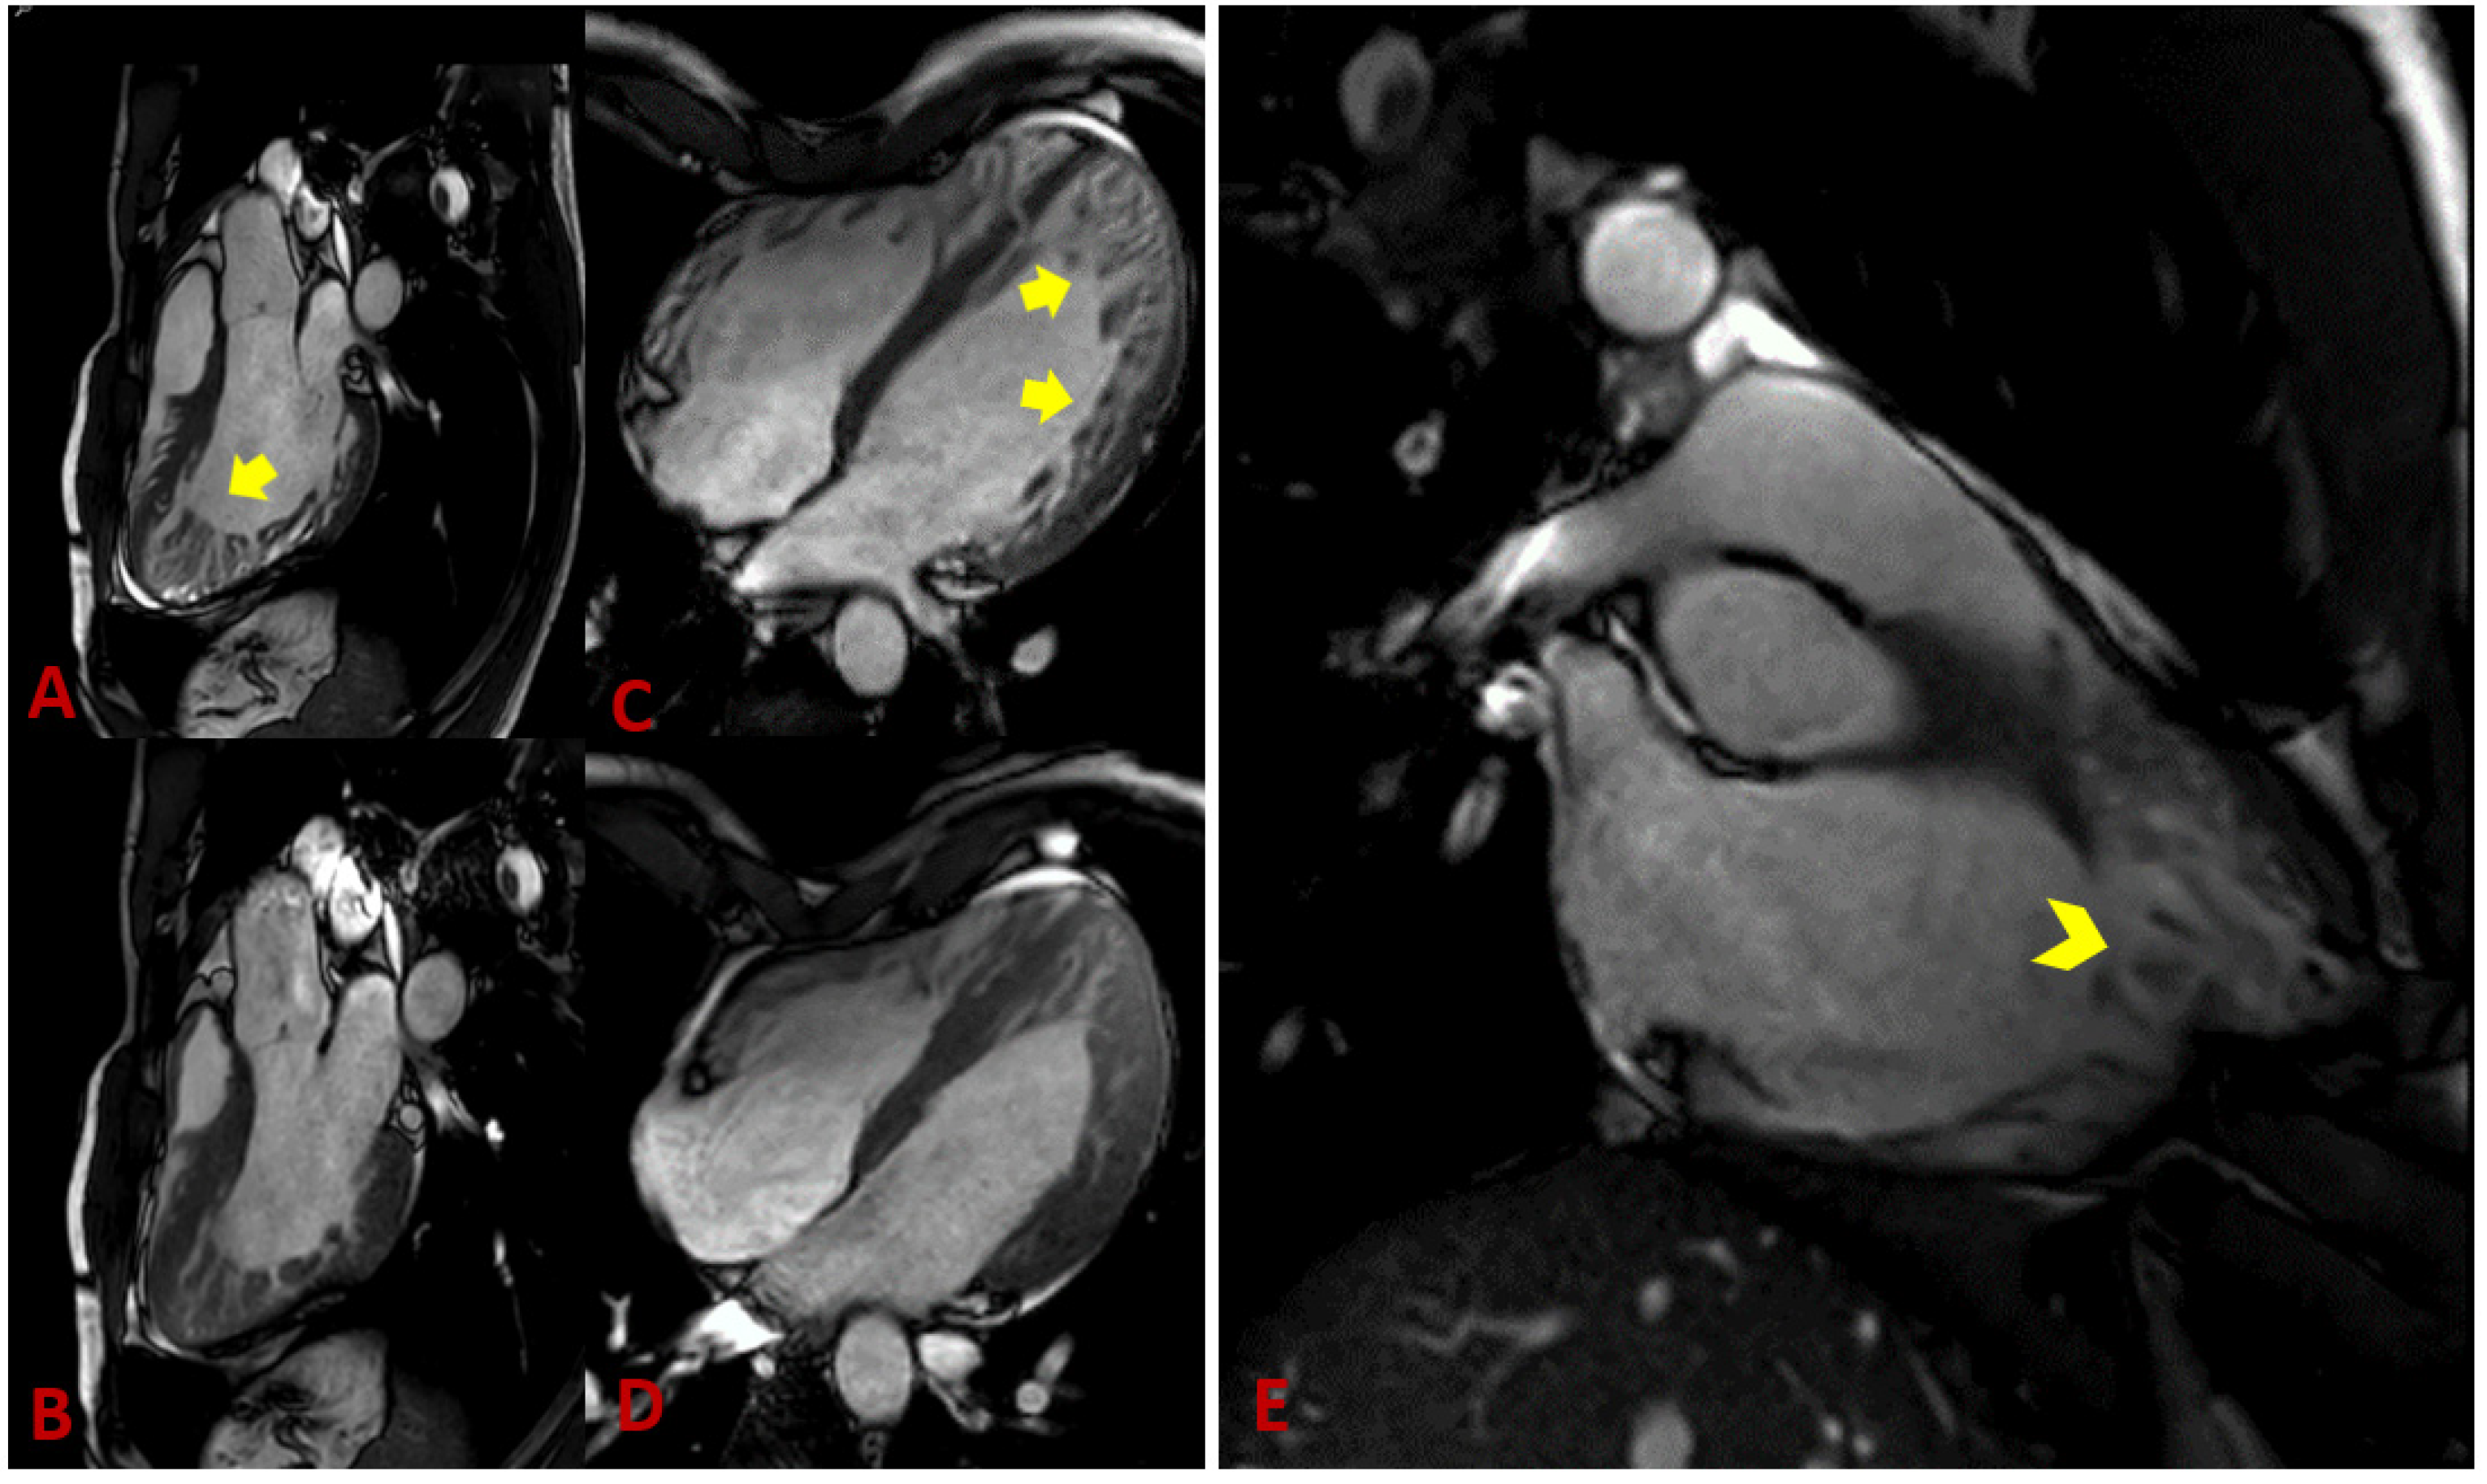

- Petersen, S.E.; Selvanayagam, J.B.; Wiesmann, F.; Robson, M.D.; Francis, J.M.; Anderson, R.H.; Watkins, H.; Neubauer, S. Left ventricular non-compaction: Insights from cardiovascular magnetic resonance imaging. J. Am. Coll. Cardiol. 2005, 46, 101–105. [Google Scholar] [CrossRef]

- Stacey, R.B.; Andersen, M.M.; St Clair, M.; Hundley, W.G.; Thohan, V. Comparison of systolic and diastolic criteria for isolated LV noncompaction in CMR. JACC Cardiovasc. Imaging 2013, 6, 931–940. [Google Scholar] [CrossRef]

- Jacquier, A.; Thuny, F.; Jop, B.; Giorgi, R.; Cohen, F.; Gaubert, J.Y.; Vidal, V.; Bartoli, J.M.; Habib, G.; Moulin, G. Measurement of trabeculated left ventricular mass using cardiac magnetic resonance imaging in the diagnosis of left ventricular non-compaction. Eur. Heart J. 2010, 31, 1098–1104. [Google Scholar] [CrossRef]

- Yun, H.; Zeng, M.S.; Jin, H.; Yang, S. Isolated noncompaction of ventricular myocardium: A magnetic resonance imaging study of 11 patients. Korean J. Radiol. 2011, 12, 686–692. [Google Scholar] [CrossRef][Green Version]

- Vogel-Claussen, J.; Rochitte, C.E.; Wu, K.C.; Kamel, I.R.; Foo, T.K.; Lima, J.A.; Bluemke, D.A. Delayed enhancement MR imaging: Utility in myocardial assessment. Radiographics 2006, 26, 795–810. [Google Scholar] [CrossRef] [PubMed]

- Jassal, D.S.; Nomura, C.H.; Neilan, T.G.; Holmvang, G.; Fatima, U.; Januzzi, J.; Brady, T.J.; Cury, R.C. Delayed enhancement cardiac MR imaging in noncompaction of left ventricular myocardium. J. Cardiovasc. Magn. Reson. 2006, 8, 489–491. [Google Scholar] [CrossRef] [PubMed]

- Jenni, R.; Wyss, C.A.; Oechslin, E.N.; Kaufmann, P.A. Isolated ventricular noncompaction is associated with coronary microcirculatory dysfunction. J. Am. Coll. Cardiol. 2002, 39, 450–454. [Google Scholar] [CrossRef]

- Dodd, J.D.; Holmvang, G.; Hoffmann, U.; Ferencik, M.; Abbara, S.; Brady, T.J.; Cury, R.C. Quantification of left ventricular noncompaction and trabecular delayed hyperenhancement with cardiac MRI: Correlation with clinical severity. AJR Am. J. Roentgenol. 2007, 189, 974–980. [Google Scholar] [CrossRef] [PubMed]

- Mavrogeni, S.I.; Markousis-Mavrogenis, G.; Vartela, V.; Manolopoulou, D.; Abate, E.; Hamadanchi, A.; Rigopoulos, A.G.; Kolovou, G.; Noutsias, M. The pivotal role of cardiovascular imaging in the identification and risk stratification of non-compaction cardiomyopathy patients. Heart Fail Rev. 2020, 25, 1007–1015. [Google Scholar] [CrossRef] [PubMed]